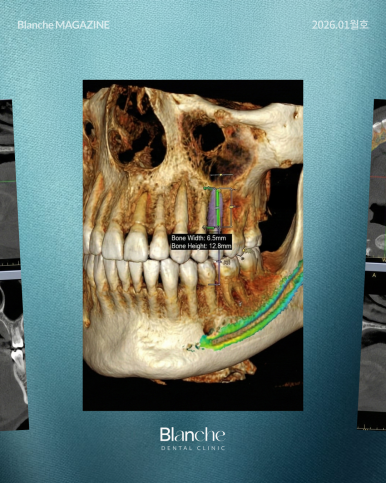

뼈이식이 진짜 필요한지는 감으로 결정하는 것이 아닙니다.

3D CT 촬영을 통해 임플란트가 들어갈 자리의 뼈 두께를 미리 입체적으로 측정해야 하는데요.

환자분도 원장님과 함께 모니터를 보며 "여기가 얇아서 뼈가 이만큼 필요하구나"라고

육안으로 확인하는 과정이 있어야 과잉진료에 대한 의구심을 지울 수 있습니다.

영상에서 강조하듯, 충분히 임플란트를 심을 수 있는 뼈의 폭(예: 6~7mm 이상)이 있는데도

뼈이식을 강권한다면 주의가 필요합니다.